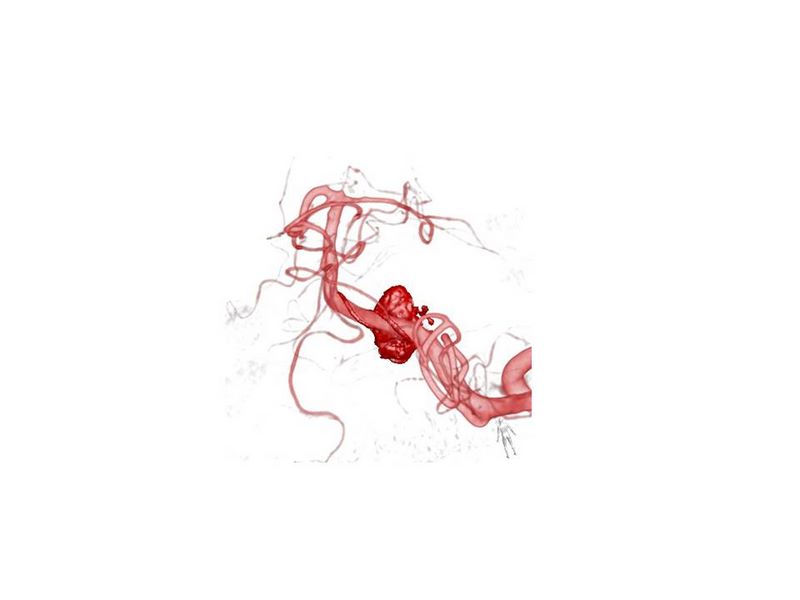

Aneurismas grandes